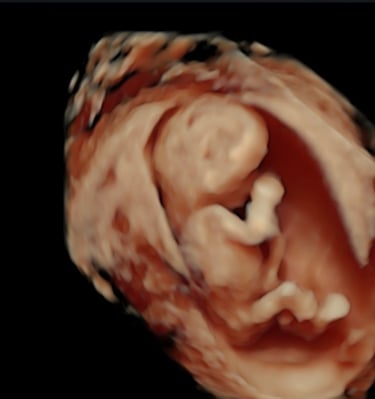

Monitoreo y cuidado especializado para el bienestar de tu bebé durante el embarazo.

Galería Neomamá

Explora momentos especiales y servicios para mamás y bebés aquí.